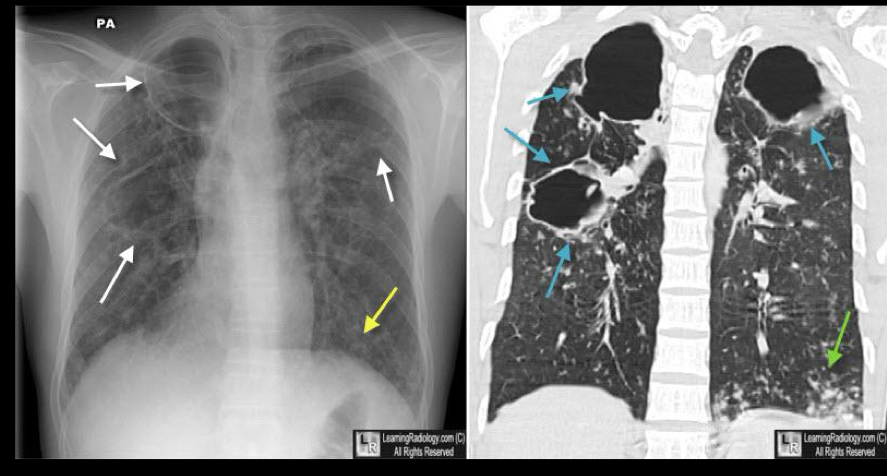

Que se ve en la reactivación

A

consolidación parcheada

Cavitaciones

Complejo de Ranke

nódulo de ghon q se asocia a ganglios calcificados en mediastino

Se ve en la reactivación